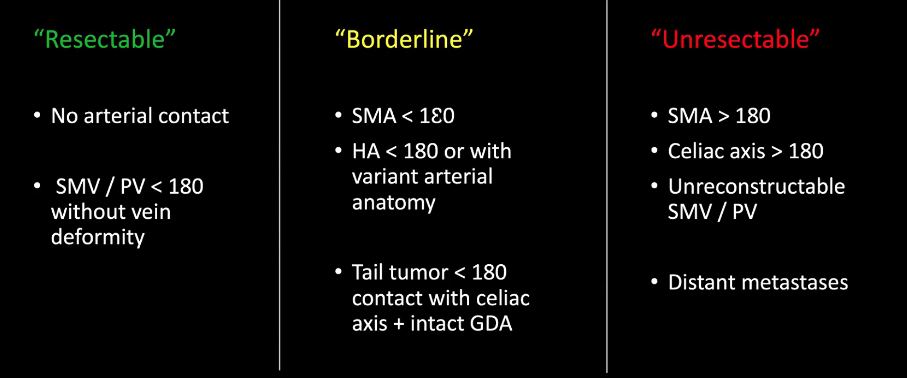

- Infiltration artérielle: <180° vs >180° et cranio-caudalement >2cm vs <2cm

- Infiltration veineuse: Contact, engainement, sténose, occlusion

Critères de résequabilité